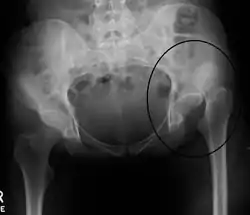

![]() أشعة سينية تظهر خلع الورك في مفصل الورك الأيسر. أشعة سينية تظهر خلع الورك في مفصل الورك الأيسر. | |

خلع الورك صعب التشخيص أحيانا لأنه لا يسبب ألم ولا تيبس بالمفصل، ولا يمكن اكتشافه إلا بمساعدة الطبيب أو الأشعة الصوتية .لذلك يقوم أطباء الأطفال بفحص جميع المواليد في اليوم الأول من الولادة لتأكد من عدم وجود خلع ولادي لمفصل الورك. وتشخيص الإصابة يختلف حسب عمر الطفل، فالتشخيص خلال أول شهرين بعد الولادة يتم عن طريق الفحص السريري للورك.وفي الآونة الأخيرة بدء التوجه لأجراء فحص بالأشعة الصوتية لمفصل الورك وذلك لاحتمالية عدم قدرة الطبيب على اكتشاف جميع المواليد المصابة عن طريق الفحص السريري . أما إذا كان عمر الطفل فوق السنة ولم يكتشف الخلع قبل ذلك فتكون أول علامة وجود خلع في أحد المفصلين وجود عرج عندما يبدأ الطفل في المشي.وقد يتأخر اكتشاف الأهل لوجود مشكلة في مشية الطفل إذا كان الخلع في كلا المفصلين، لعدم وجود عرج واضح في المشية وقد يلاحظ الأهل فقط أن هناك شئ ما غير طبيعي وقد لا يذهبون لطبيب حتى يبدأ الشك لديهم يصل إلى حد اليقين أن هناك مشكلة في مشية الطفل. يمكن التأكد من وجد الخلع بإجراء أشعة سينية للحوض ومفصل الورك .